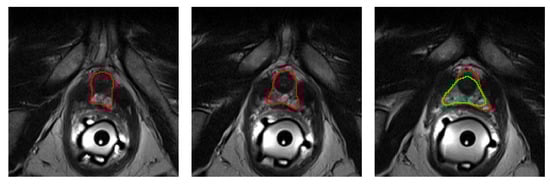

2.4. Deep Supervision

To further improve the performance of the CNN, a simple implementation of Deep Supervision [27] is used. Unlike regular CNNs, which predict the segmentation mask from the last layer only, deeply supervised CNNs attempt to predict it from several intermediate layers as well. In Figure 2 this is implemented by the branches to the right of the decoder, which take the activation maps at two points along the decoder, reduce the number of channels to one by means of a “bottleneck” convolution, and then upsample them to the CNN output resolution using Nearest Neighbors interpolation. During training, the final output of the CNN is averaged with these intermediate predictions while, during inference, only the final output is considered. A similar implementation for this technique is also successfully used by [15]. Figure 3 shows the GT mask of a prostate MR image, as well as the final and intermediate predictions, which are used for Deep Supervision. As it can be seen, intermediate predictions resemble a downscaled version of the final mask.

Figure 3. From left to right: first intermediate prediction, second intermediate prediction, third (and final) prediction, and original MR prostate image with GT label.